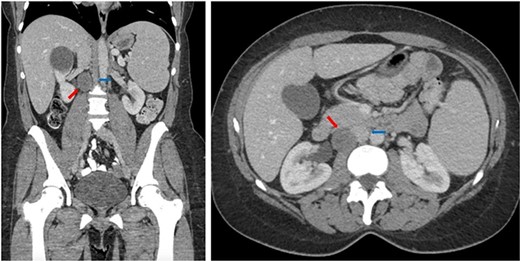

Subsequently, a computed tomography (CT) of the abdomen and pelvis revealed a hypodense lesion located posterolateral to the inferior vena cava (IVC) measuring 28 × 25 mm (see Fig. 1).

Coronal (left) and axial (right) CT of the abdomen and pelvis showing the retrocaval schwannoma (red arrow) and IVC (blue arrow).